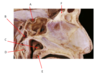

A.

B. Chorda Tympani (branch of CN 7)

C. Inferior Alveolar n. (branch of CN 5.3)

D. Facial n. (CN 7)

E. Lingual n. (branch of CN 5.3)

F. Posterior Superior Alveolar n. (branch of CN 5.2)

G.

H. Infraorbital n. (branch of CN 5.2)

I. Mental n. (branch of CN 5.3)

Which structure is labeled by B?

Mylohyoid